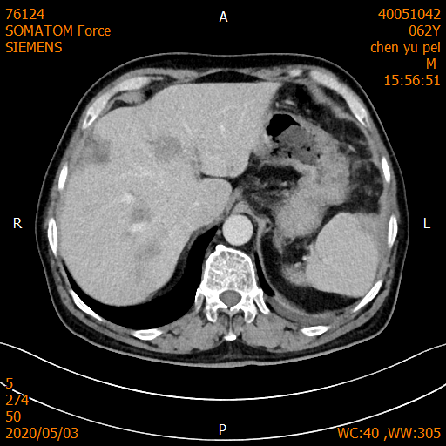

2020-02-04 CT

肝脏多发异常强化灶,考虑转移。

横结肠-降结肠交界处壁增厚强化,请结合消化道检查,腹腔部分肠管扩张积气积液,可见气液平,请结合临床。

2020-02-27 增强CT报告:

肝脏多个略低密度影,考虑转移灶,结合临床;脾脏外缘积液;

胆囊略大;前列腺钙化灶;腹腔积液;左中下腹术后改变;

腹盆腔、后腹膜多发淋巴结,局部肿大;双侧腹股沟小淋巴结。

2020-05-03 增强CT示胸部+全腹部增强CT:1、结肠癌术后:左侧腹造瘘改变,左上腹网膜增厚,请结合临床;2、肝脏多发转移,较前缩小。